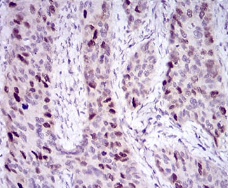

IHC    1/200 - 1/1000